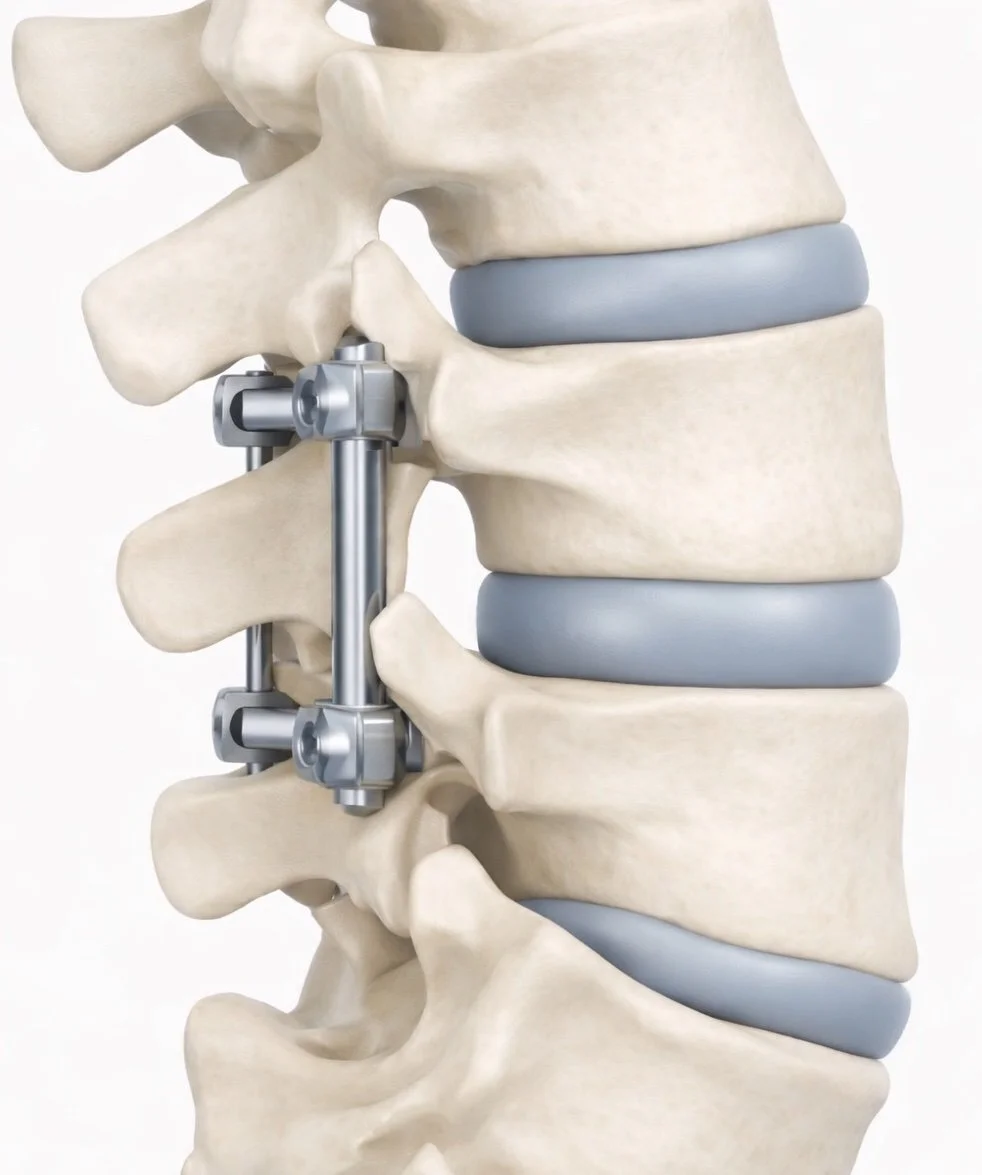

A detailed illustration of a spinal fusion surgery showing metal rods, screws, and artificial disc replacements in the lumbar spine.

What Is Posterior Lumbar Decompression and Fusion?

Posterior lumbar decompression and fusion is a procedure performed through an incision in the back of the spine.

The surgery has two main goals:

1. Relieve pressure on the nerves

2. Stabilize the spine

First, the surgeon removes bone and thickened tissue that are compressing the spinal nerves (decompression).

Next, the affected vertebrae are stabilized using screws, rods, and bone graft, allowing the bones to fuse together over time.

Fusion helps prevent excessive movement between the vertebrae and can improve spinal stability.